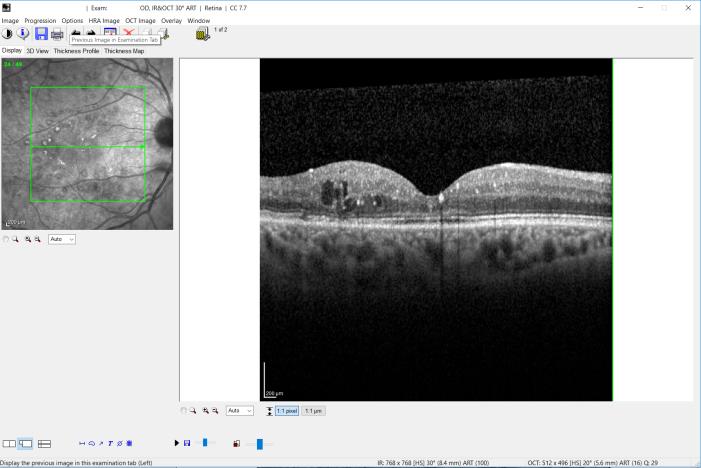

Η πλέον σημαντική εξέταση για τη διάγνωση της διαβητικής αμφιβληστροειδοπάθειας είναι η βυθοσκόπηση σε μυδρίαση. Συγκεκριμένα, διαστέλλεται η κόρη των οφθαλμών με τη χρήση ειδικών κολλυρίων και μετά εξετάζεται ο αμφιβληστροειδής για διάφορα παθολογικά σημεία στην σχισμοειδή λυχνία. Με τον τρόπο αυτό γίνεται ο διαχωρισμός των διαβητικών με οφθαλμική προσβολή από τα υγιή μάτια. Ακριβώς επειδή ιδίως στα αρχικά στάδια εξελίσσεται τελείως ασυμπτωματικά η νόσος, θεωρείται υψίστης σημασίας η βυθοσκόπηση τουλάχιστον μια φορά το χρόνο σε όλους ανεξαιρέτως τους διαβητικούς. Στους ασθενείς με παθολογικά σημεία απαιτούνται συχνά πιο ειδικές εξετάσεις για την εκτίμηση της βαρύτητας της νόσου. Μια τέτοια είναι η φλουοροαγγειογραφία, με την οποία εξετάζονται τα αγγεία και η αιμάτωση του αμφιβληστροειδούς, αφού χορηγηθεί ενδοφλεβίως μια ειδική χρωστική ουσία (φλουορεσεΐνη) και ληφθούν φωτογραφίες του βυθού σε συγκεκριμένες χρονικές στιγμές. Μια άλλη ειδική και πολύ σημαντική εξέταση, ιδίως για ασθενείς με μειωμένη όραση, είναι η οπτική τομογραφία συνοχής (OCT). Πρόκειται για μια πολύ μοντέρνα εξέταση, τελευταίας τεχνολογίας, που εστιάζεται στην ωχρά κηλίδα, το κεντρικό δηλαδή και πιο ευαίσθητο τμήμα του αμφιβληστροειδούς, για να εντοπίσει τυχόν συσσωρεύσεις υγρού, λίπους κτλ., καθιστώντας έτσι δυνατή τη διάγνωση και την παρακολούθηση της εξέλιξης της λεγόμενης διαβητικής ωχροπάθειας. Δευτερεύουσες εξετάσεις είναι η γωνιοσκοπία (για την ανίχνευση τυχόν νεοαγγείων στην γωνία του προσθίου θαλάμου) ή ο υπέρηχος (για την αποκλεισμό αποκόλλησης του αμφιβληστροειδούς, όταν αυτό δεν είναι με τη βυθοσκόπηση εφικτό, λόγω μιας υαλοειδικής αιμορραγίας). Οι παραπάνω εξετάσεις δίνουν στον οφθαλμίατρο πληροφορίες για την βαρύτητα και τα συνολικά χαρακτηριστικά της νόσου του κάθε διαβητικού, ώστε αναλόγως να εφαρμοστεί στον κάθε ασθενή εξατομικευμένη θεραπεία, ανάλογα των αναγκών του.

OCT διαβητικού ασθενούς με οίδημα στην ωχρά